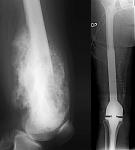

• Tumor total endoprosthesis (TEP) of all large joints and bones

• Resection of benign and malignant tumors of the bone and soft tissue

• Reconstruction of bone defects by biological procedures (from spongiosaplasty to bone transfer)